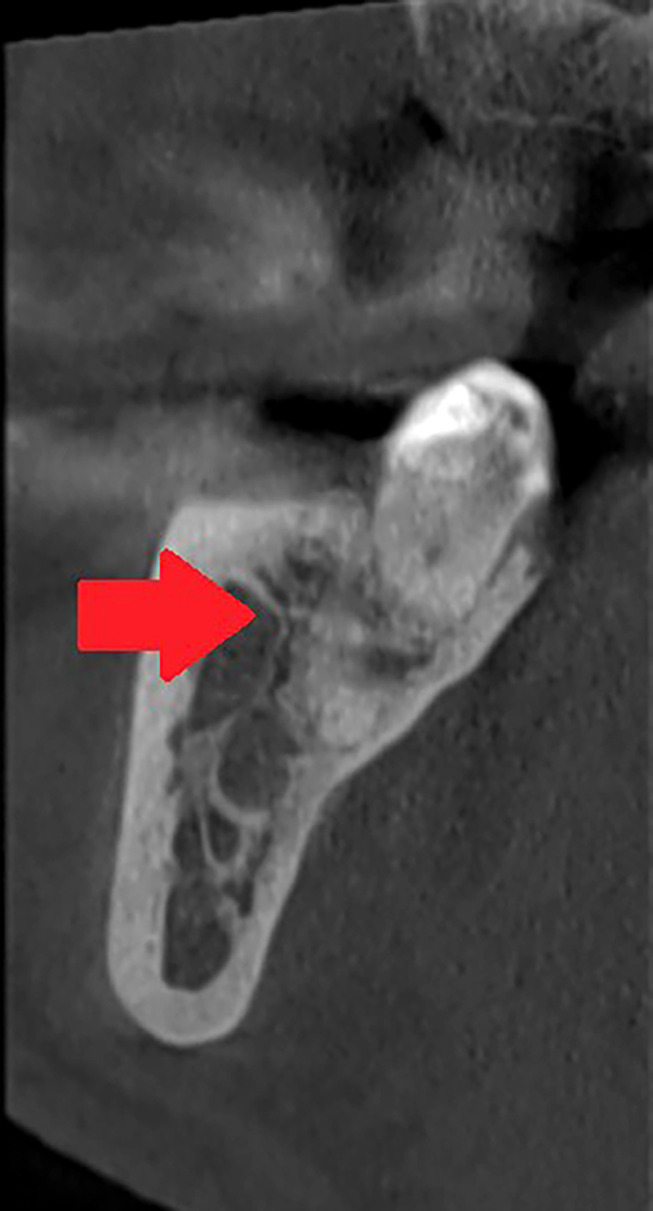

背景/目的:下颌骨管(MC)的解剖已经在文献中被广泛描述。许多研究对其解剖变异和异常进行了研究。多年来,人们使用了不同的方法来研究下颌骨,并提出了不同的分类方法。患者和方法:进行文献检索,以确定有关下颌管,双裂和三裂下颌管的文章。这项搜索使用了PUBMED和WoS计算机数据库,时间从1931年到2023年。不属于检索范围的研究被排除在外,例如那些摘要为初步评价提供的信息不足的研究。另外,一些没有被数据库检索到的文章,包括病原学方面的文章,是手工输入的。对于所有被认为符合条件的研究,检索并下载了文章全文。结果:根据文献分析,MC的变异可分为二裂MC、三裂MC、下颌内副管和牙管。下颌外颊管和舌管需要重点研究,因为它们非常频繁,数量众多,并且具有营养功能。结论:本文强调了MC变异的一些重要的放射学和解剖学方面,以及它们与实际分类的临床意义。有些分类仅具有统计和历史价值,对牙医和口腔外科医生没有实际用途。如果不能正确识别重复可能会导致围手术期并发症。需要对MC的前、中、后三个部位的不同变化进行新的研究。提出了一种更有用的分类方法。

Results: Based on the analysis of the literature, the variants of the MC should be classified as bifid MC, trifid MC, intramandibular accessory canals and dental canals. Extramandibular buccal and lingual canals require focused research, because they are very frequent, numerous, and they have nutrient functions.